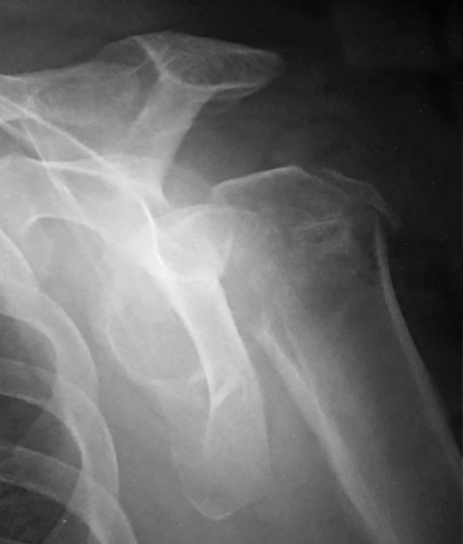

Pre-op

- 75-year-old female, autonomous

- Acute left proximal humeral fracture 2021

- 3-part fracture acc. to Neer classification

- with comminuted greater tuberosity

- Indication for RSA